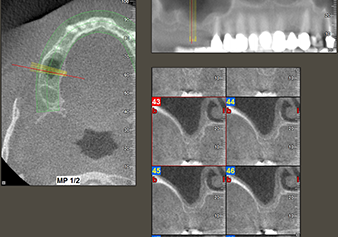

Una paziente di 49 anni, non fumatrice e con un'anamnesi priva di elementi rilevanti, è stata indirizzata al nostro studio di chirurgia orale per l'estrazione chirurgica del dente 16 ed il successivo impianto. Dopo l'estrazione, la paziente ha accusato dei lievi dolori causati dalla sinusite, motivo per cui abbiamo inizialmente aspettato sei mesi prima di procedere con l'intervento. L'altezza ossea residua in corrispondenza della posizione dell'impianto misurava 3-4 mm (Fig. 1 e 2).

Fig.2: il DVT mostra le corrette dimensioni in ogni vista assiale (sinistra), laterale (in alto) e trasversale (destra). La membrana del seno mascellare è ancora leggermente ispessita.